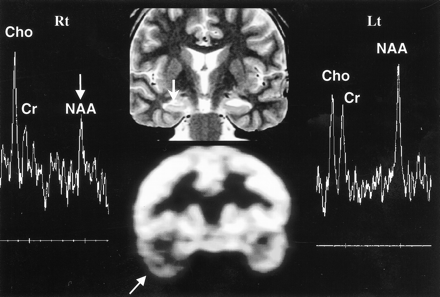

Discordant MRS with MR imaging and PET in left hippocampal sclerosis. Oblique coronal T2-weighted MR image (top row, middle) shows left hippocampal atrophy (arrow), in concordance with PET scan (bottom row, middle), which shows decreased metabolism in left temporal lobe (arrow). However, the MR spectrum from the left hippocampus (Lt) appears within normal range (false-negative finding), based on the abnormal criteria of an NAA/Cho ratio of 0.8 or less or an NAA/Cr ratio of 1.0 or less. The MR spectrum from the left hippocampus (Lt) shows a decrease in NAA/Cho and NAA/Cr ratios (arrow) on right side (Rt) (false-positive finding)